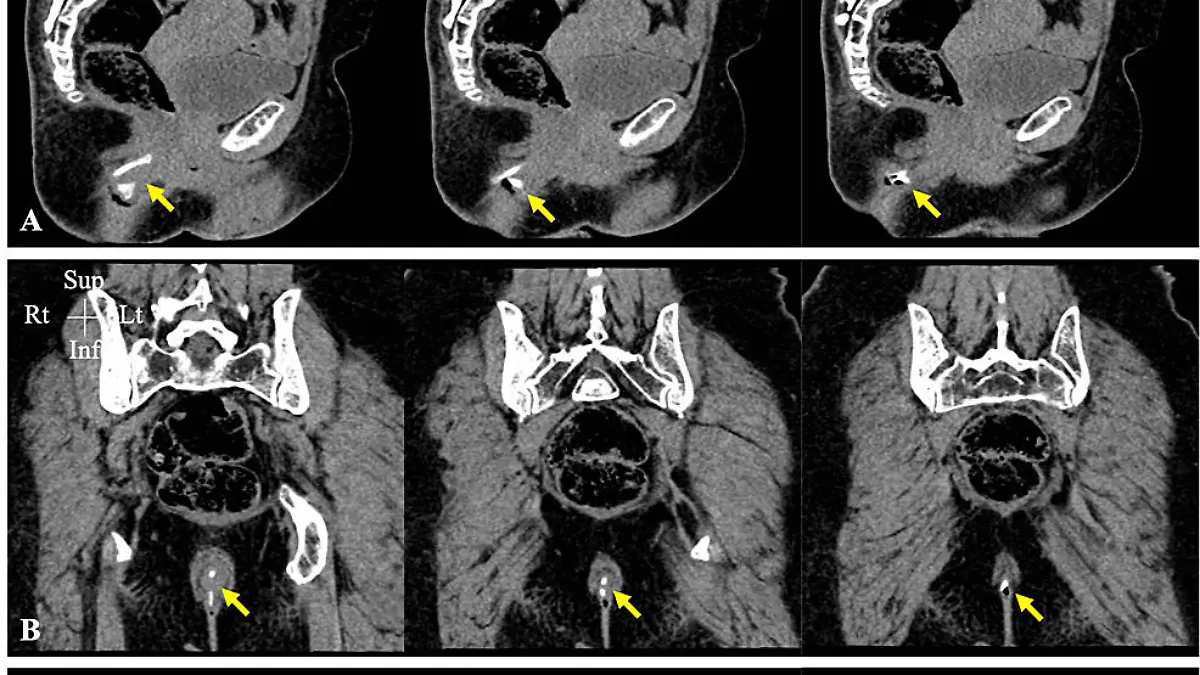

Zwar hatte es der knochige Übertäter fast geschafft, den Körper der Frau ohne Schaden zu durchqueren, am Ende verkeilte er sich aber so, dass er aus ihrem Po herausragte. Die Frau wurde kurzerhand ins Krankenhaus eingeliefert, wo eine Computertomographie (CT) schließlich die vollen Ausmaße ans Licht brachte: 5 x 2,5 x 3 cm groß war der Hühnerknochen, wie die medizinische Fachzeitschrift „Cureus“ berichtete.